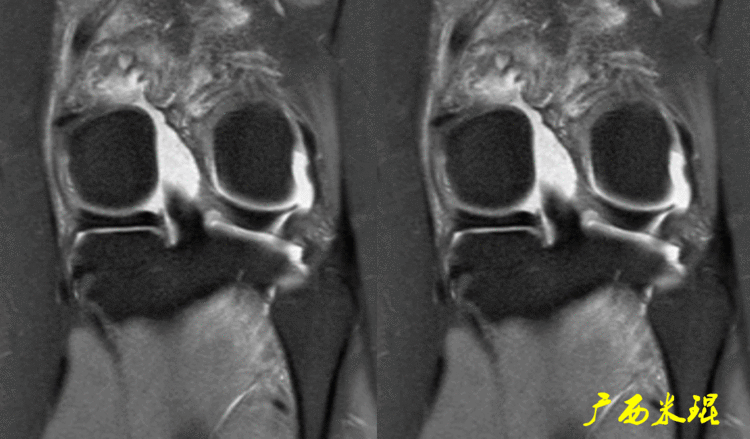

(1)假桶柄MR冠状位上偏后的层面,“C”形或“O”形的内外侧半月板偏后侧层面有可能同时扫描到半月板体部和后角,容易误诊为桶柄状撕裂,而矢状位或横断位上半月板形态是正常的。

下面这张MR冠状位显示为内侧半月板后角的假桶柄,其母体(图片中内侧的那一部分半月板)并没有变小、形态及信号均正常。

下面这张MR冠状位显示为外侧半月板后角的假桶柄,尽管在髁间窝发现半月板信号,但其母体(图片中外侧的那一部分半月板)并没有变小、形态及信号均正常。